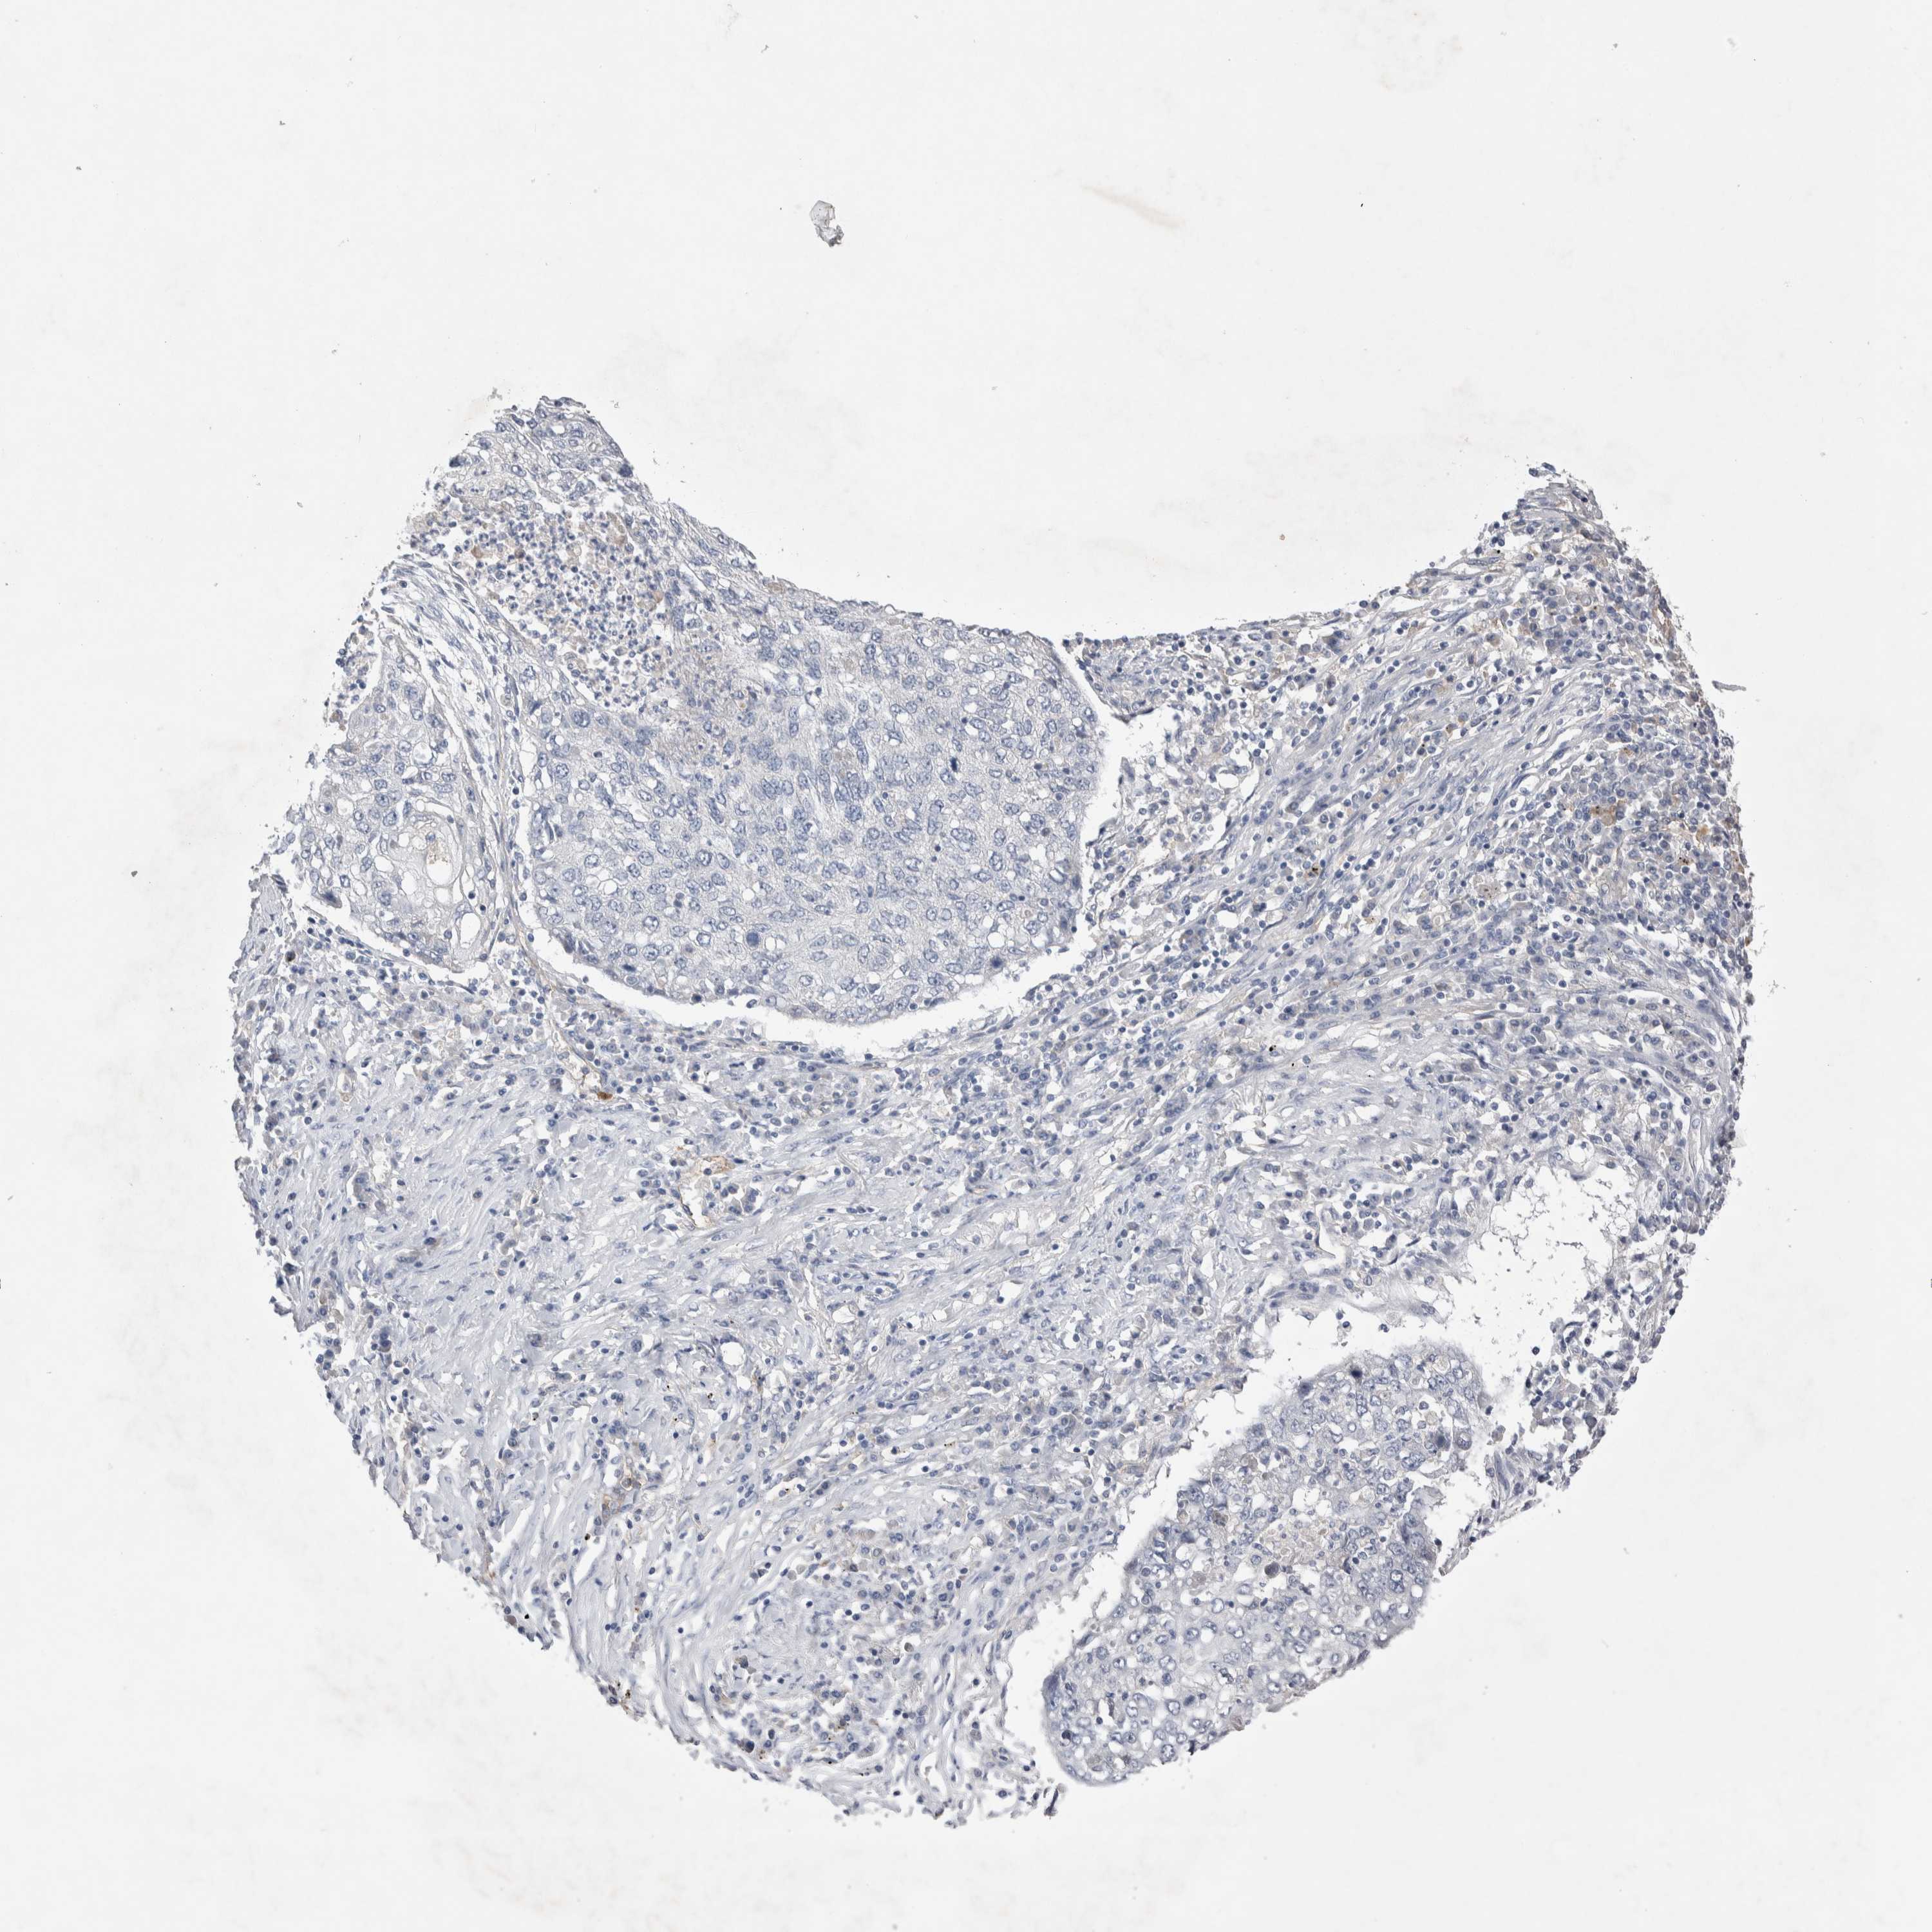

LUNG SQUAMOUS CELL CARCINOMA (TCGA) - Interactive survival scatter ploti

The Survival Scatter plot shows the clinical status (i.e. dead or alive) for all individuals in the patient cohort, based on the same data that underlies the corresponding Kaplan-Meier plots. Patients that are alive at last time for follow-up are shown in blue and patients who have died during the study are shown in red.

The x-axis shows the expression levels (FPKM) of the investigated gene in the tumor tissue at the time of diagnosis. The y-axis shows the follow-up time after diagnosis (years). Both axes are complimented with kernel density curves demonstrating the data density over the axes. The top density plot shows the expression levels (FPKM) distribution among dead (red) and alive patients (blue). The right density plot shows the data density of the survived years of dead patients with high and low expression levels respectively, stratified using the cutoff indicated by the vertical dashed line through the Survival Scatter plot. This cutoff is automatically defined based on the FPKM cutoff that minimizes the p-score. The cutoff can be changed by dragging the vertical line or by entering a cutoff value in the square labeled "Current cut-off".

Under the Survival Scatter plot the p-score landscape (black curve; left axis) is shown together with dead median separation (red curve; right axis). Dead median separation is the difference in median mRNA expression between patients who have died with high and low expression, respectively. It is calculated as follows: median FPKM expression of dead patients with high expression - median FPKM expression of dead patients with low expression. This is intended to aid the user in visually exploring custom cutoffs and the associated p-scores and dead median separation.

Individual patient data is displayed and can be filtered by clicking on one or more of the category buttons on the top of the page. Categories describing expression level and patient information include: high, low, alive, dead, female, male and tumor stages. The scale of the x-axis can be toggled between linear and log-scale by clicking on the "x log" button. Mouse-over function shows TCGA ID, patient information and mRNA expression (FPKM) for each patient.

& Survival analysisi

Kaplan-Meier plots summarize results from analysis of correlation between mRNA expression level and patient survival. Patients were divided based on level of expression into one of the two groups "low" (under cut off) or "high" (over cut off). X-axis shows time for survival (years) and y-axis shows the probability of survival, where 1.0 corresponds to 100 percent.

CEP131 is not prognostic in Lung Squamous Cell Carcinoma (TCGA)

: 13.35

P scorei

N/A

Average pTPM 14.1

Number of samples 489